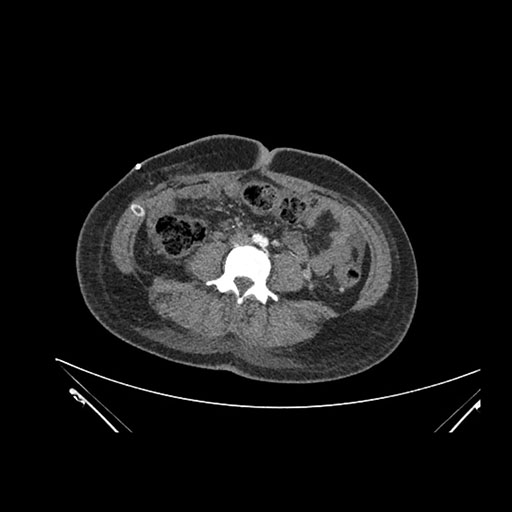

Axial Arterial

Axial Venous